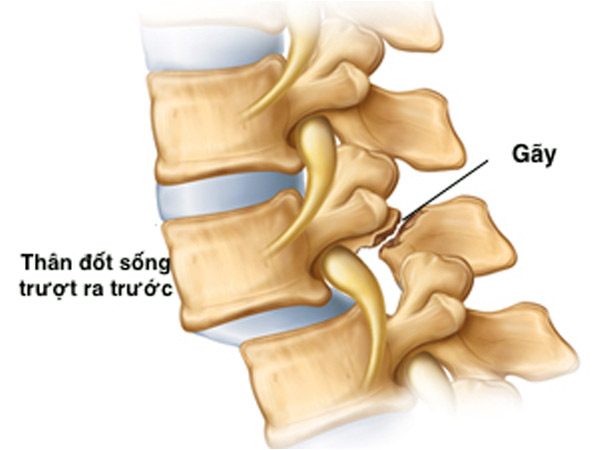

Trượt đốt sống (TĐS) là hiện tượng dịch chuyển của đốt sống phía trên so với phía dưới. Hầu hết các bệnh nhân TĐS thắt lưng diễn biến âm thầm không có triệu chứng. Khi người bệnh đến viện khám thường đã có triệu chứng chèn ép thần kinh, đau cột sống thắt lưng do mất vững, giai đoạn muộn có thể tổn thương thần kinh nặng hơn như liệt ở các mức độ khác nhau.

Có nhiều nguyên nhân trượt đốt sống khác nhau như: TĐS do thoái hóa, TĐS do khuyết hở eo, TĐS sau mổ giải ép mở cung sau, TĐS do khối u … Tuy nhiên hay gặp nhất vẫn là TĐS do khuyết hở eo và thoái hóa [1].

Có 2 BN (6,7%) bị TĐS do khuyết eo, 93,3% do thoái hóa. Trượt độ I chiếm 86,7%, còn lại độ II và độ III. Chiều cao đĩa đệm trước mổ trung bình 8,0 ± 2,5 mm (3 – 11 mm). 27 BN (90%) có hình ảnh hẹp ống sống, 03 BN (10%) có hình ảnh hẹp lỗ liên hợp trên phim MRI.

Xquang: Trên phim Xquang cột sống thắt lưng có 93,3% BN bị TĐS do thoái hóa, chỉ có 2 BN (6,7%) bị TĐS do khuyết eo gặp ở bệnh nhân trẻ tuổi. Đánh giá mức độ TĐS theo Meyerding, trượt độ I chiếm 86,7%, còn lại độ II và độ III. Kết quả này tương đồng với một số nghiên cứu khác như: Phan Trọng Hậu trượt độ I là 51,4%, độ II là 41,4%, độ III là 7,2%; Phan Minh Đức có kết quả trượt độ I là 69%, độ II là 30%, độ III là 1%.

Cộng hưởng từ: Nghiên cứu của chúng tôi có 27 BN (90%) có hình ảnh hẹp ống sống. Nguyên nhân gây hẹp là do thân đốt sống trượt, đĩa đệm thoát vị, phì đại mấu khớp và dây chằng vàng do thoái hóa. Nghiên cứu của Phan Trọng Hậu cho kết quả hẹp ống sống trên CHT là 44,3%, nghiên cứu của Edelson gặp 32% [1]. Hẹp ống sống, lý do phổ biến cho phẫu thuật vùng thắt lưng ở người lớn trên 65 tuổi, bệnh nhân thường có biểu hiện đau cách hồi thần kinh, liên quan nhiều đến tư thế ngồi, đi lại và vận động. Hẹp lỗ liên hợp gây chèn ép rễ do di lệch trượt của thân đốt sống về phía trước và do giảm chiều cao đĩa đệm, ngoài ra mấu khớp phì đại gây nên. Trong nghiên cứu của chúng tôi hình ảnh hẹp lỗ liên hợp có 10% bệnh nhân. Như vậy có thể thấy hẹp lỗ liên hợp là một trong những nguyên nhân gây đau rễ thần kinh.